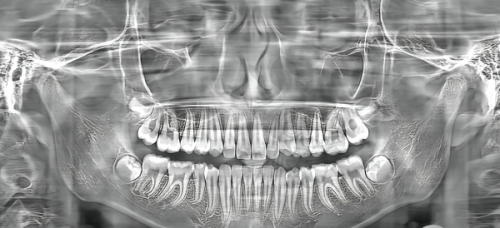

根管治疗(又称牙髓治疗)是治疗牙髓炎、坏死牙髓、根尖周围病变等常见可怕“牙痛症”的有效方式。医生会在局麻下打开患牙,移除感染的牙髓与根管内坏死组织,通过扩张、消毒、填充根管封闭感染途径。

① 口腔数字影像检查 ——精细判断牙髓感染范围及牙根结构